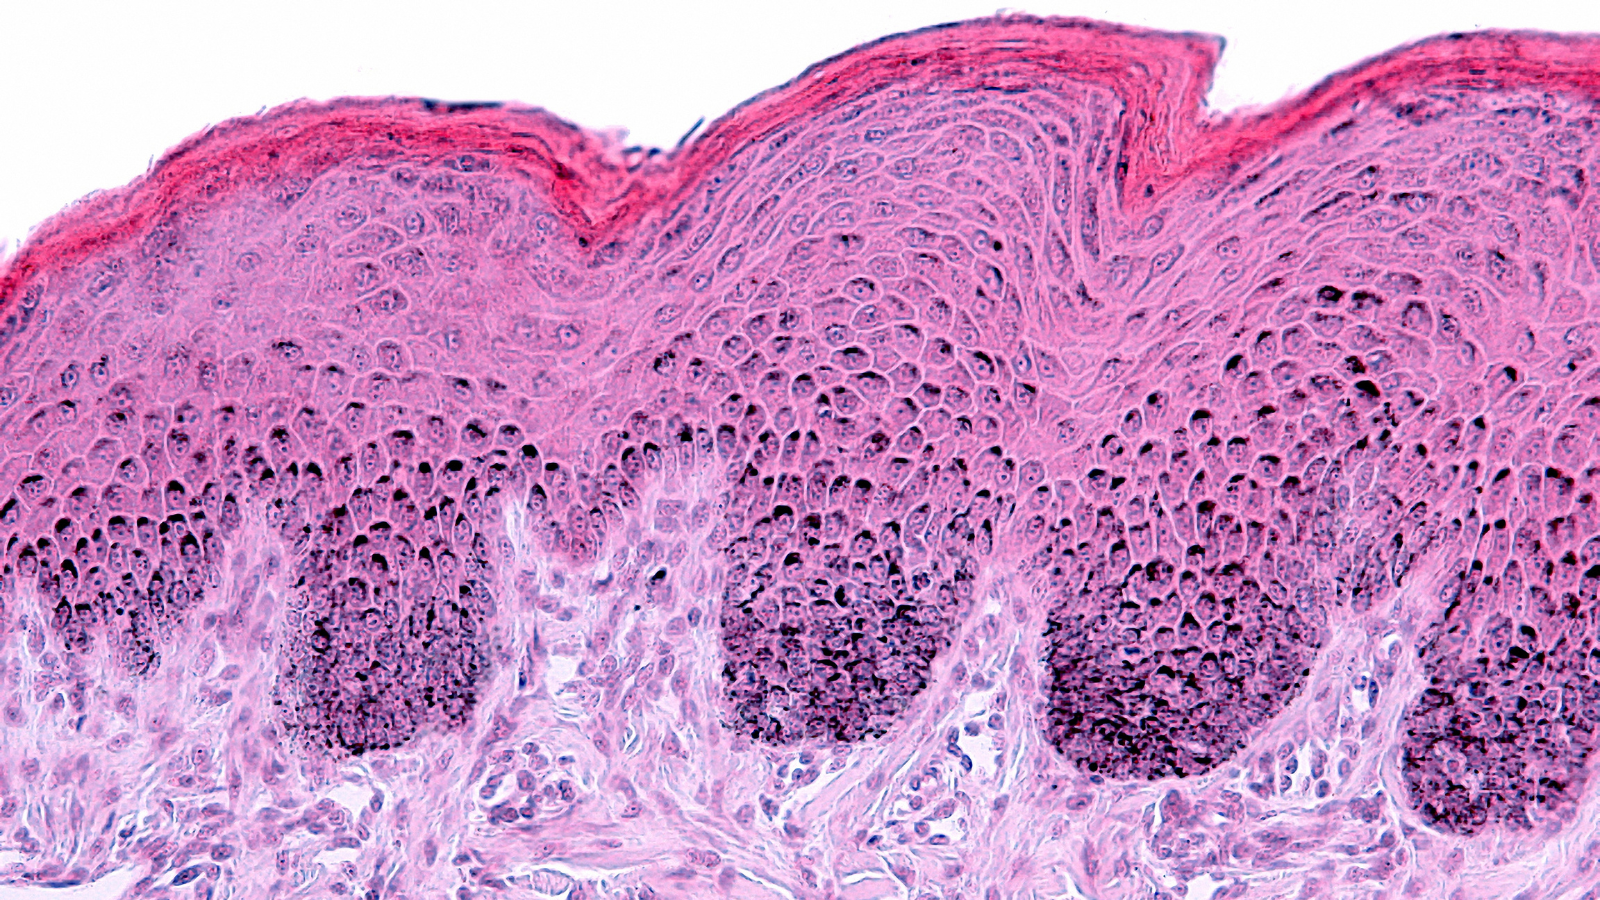

• Microbiological analyses to verify the absence of contamination

• Microbiological analyses: hygiene control, conservation tests